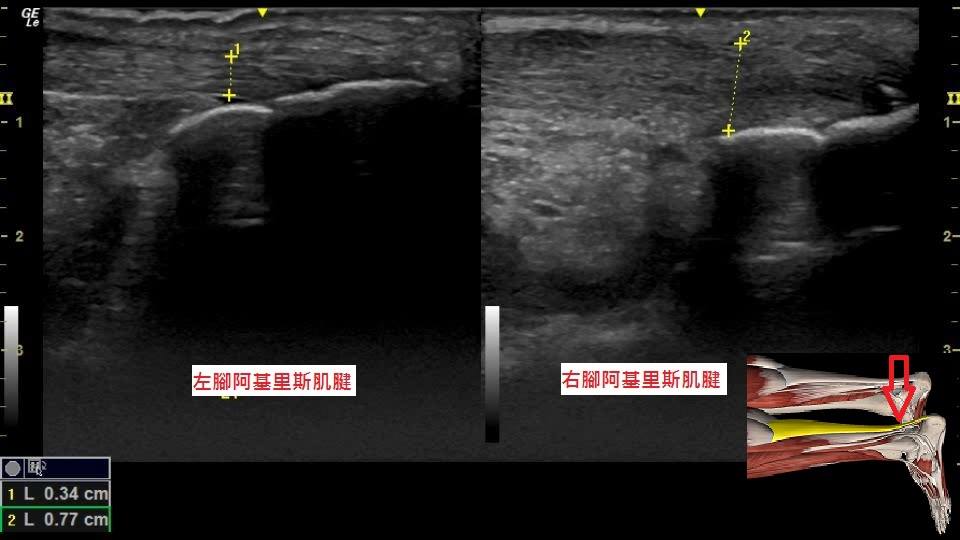

【圖4】腳後跟疼痛半年的患者,超音波發現後腳筋(阿基里斯肌腱)腫脹合併撕裂傷。